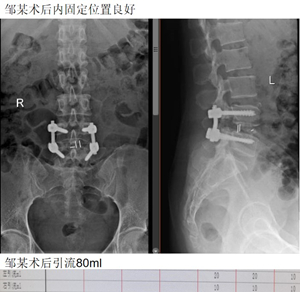

最后是邹某,双下肢疼痛10余年,加重伴麻木2月。入院行L4/5肌间隙入路下腰椎融合术。术后3天拔管,5天出院。

术后引流仅80ml。